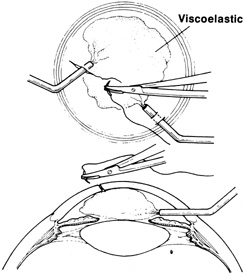

Tissue adhesive should be applied to a dry, deepithelialized bed. A capillary microapplicator or fine-gauge disposable needle is used to apply a very thin film of adhesive over the site (Fig. 3). Alternatively, adhesive may be applied using a sterile 2- to 4-mm polyethylene or silicone disc affixed to the end of an applicator stick with sterile ophthalmic ointment. The disc may be left in place or removed with care. Three to five minutes are required for polymerization of the adhesive. A bandage soft contact lens is applied for comfort and to prevent the glue from dislodging. While the contact lens is in place, a prophylactic antibiotic drop is administered. Over time, the tissue adhesive dislodges spontaneously as the wound surface reepithelializes. Alternatively, it may be gently removed with forceps after adequate stromal healing has occurred.